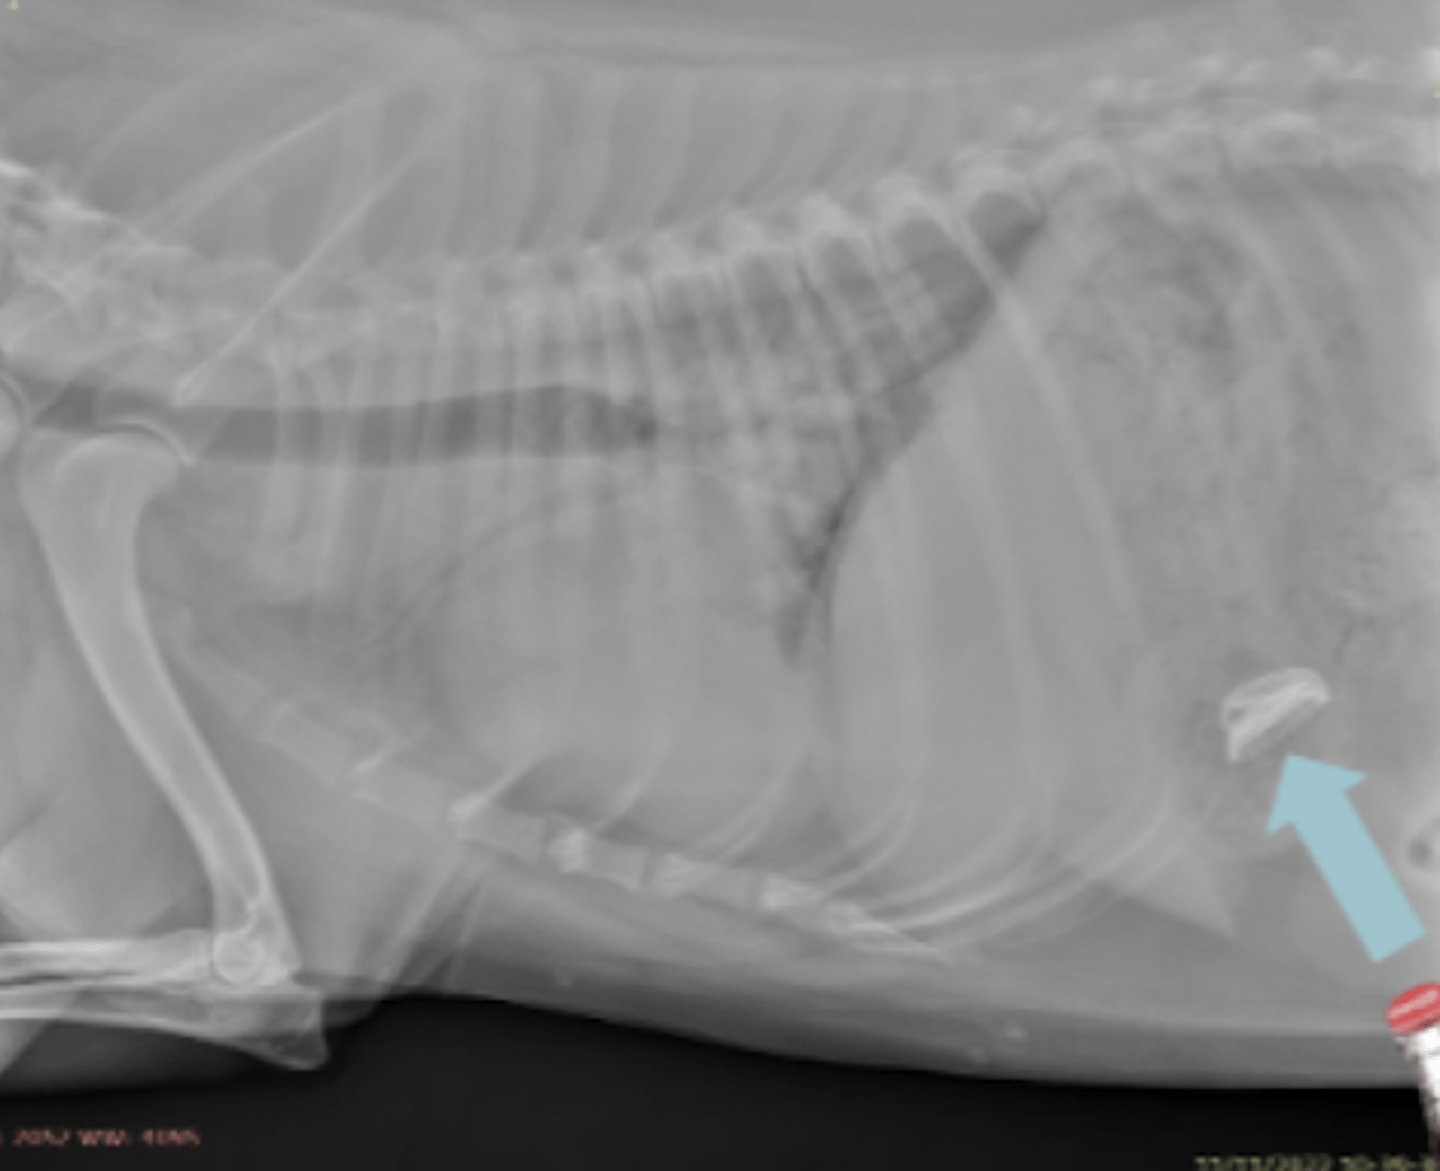

megaesófago, por cuerpo extraño

patología:

radiopaco.

(blanco)

en radiología simple, un cuerpo extraño aparece con radiopacidad:

cuerpo extraño en estomago